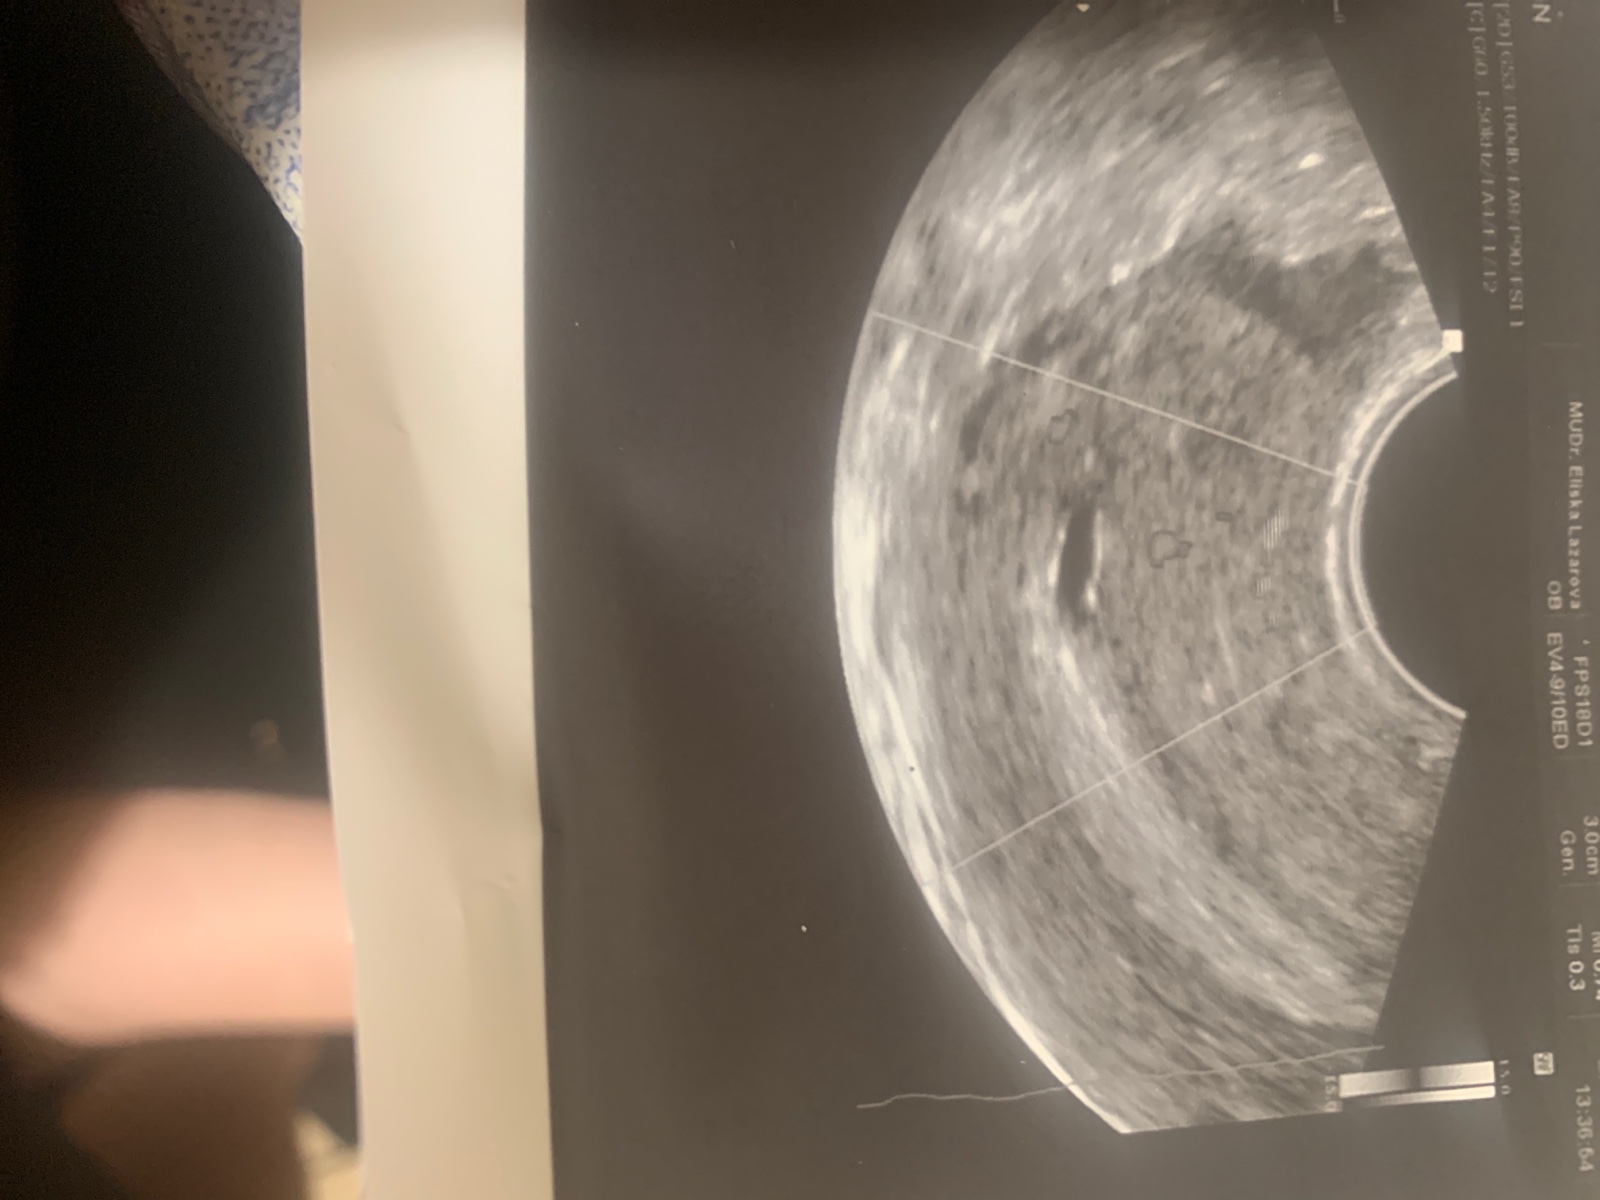

Dobrý večer dámy... Moc Vás prosím o vaši radu/zkušenosti co se týká údajného zaniklého těhotenství ... Má poslední menzess byla 18.10. od té doby nic, nějak od 3.11. mě začaly pobolivat prsa a sem tam sem měla divné tlaky v podbrisku. Zkoušela sem si dělat test 11.11. a měla jsem tam slaboulinkou čárku tak sem si řekla ze počkám do menstruace a pak to zkusím znovu, jelikož mám dost těžkou fyzicky náročnou práci nechtěla jsem nic podcenit. Další test sem si delala 17.11 a tam už ta druhá čárka byla více viditelná menzes se měla dostavit kolem 20.11 a do teď nic. Byla jsem u lékaře 18.11 šla jsem na preventivní prohlídku tam mi řekl ze je možné ze jsem těhotná ale nic moc tam vidět nejde vzal mi testy na HCG v pátek sem volala o výsledky a byly 68,8. Což je málo pozval mě další týden znovu na krev 25.11 sem byla znovu na krvi a měla jsem HCG jen 257. Takže mi pan doktor řekl ze jde nejspíš o zamlkle těhotenství.Večer sem začala krvacet a měla šílené bolesti v podbrisku tak sem jela na pohotovost kde mi řekl doktor ze potrat to nebyl, hrdlo mám uzavřené a to něco má cca 3-4mm ale podle mě poslední MS to nesedí. Dal mi léky píchl injekci na zastavení krvácení s tím ze si mám zajít potom ke svému doktorovi. K němu sem šla a ten mi řekl ze mám počkat na MS ze to odejde samo.Ze už se nedá nic dělat. Od včerejšího dne 27.11 mam slabe krvácení , spíše jen takové splnění. Cyklus sem si počítala mám ho asi 33 dnů. Moc se v tom nevyznám, mám menzes pokaždé jinak. Snažíme se s přítelem už dlouho bylo by to naše druhé, dcerka už má 7. Prosím Vás o radu, je tam ještě nějaká nadej ze by se to vzpamatovalo a HCG mi narostlo? Moc všem děkuji, jsem už zoufalá :( . Příkladam svou fotku z ULT, kde mi bylo řečeno ze tam bohužel nic není, ze je to ztracené . :(

@baarus21 ano test sem si delala po tom krvácení , přiložil foto. Taky si myslím ze tam naděje je, podle me ovulace to tak vychází. Ty 3-4mm + týden těhotenství apod. On mě to vůbec nenechal vysvětlit. Jenže včera sem si dělala test, a ten mi už ukázal slabší, ale divné je ze mě prsa stále bolí :(.